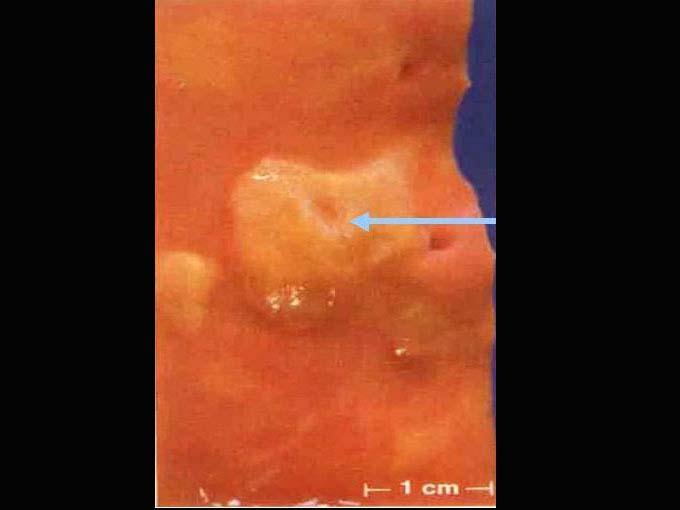

主动脉粥样硬化巨检如图,镜下观如图所示,该病变最佳名称为 ( )A.脂纹B.纤维斑块C.粥样斑块D.粥瘤性溃疡E.动脉瘤形成

问题 主动脉粥样硬化巨检如图,镜下观如图所示,该病变最佳名称为 ( )

选项 A.脂纹 B.纤维斑块 C.粥样斑块 D.粥瘤性溃疡 E.动脉瘤形成

答案 D